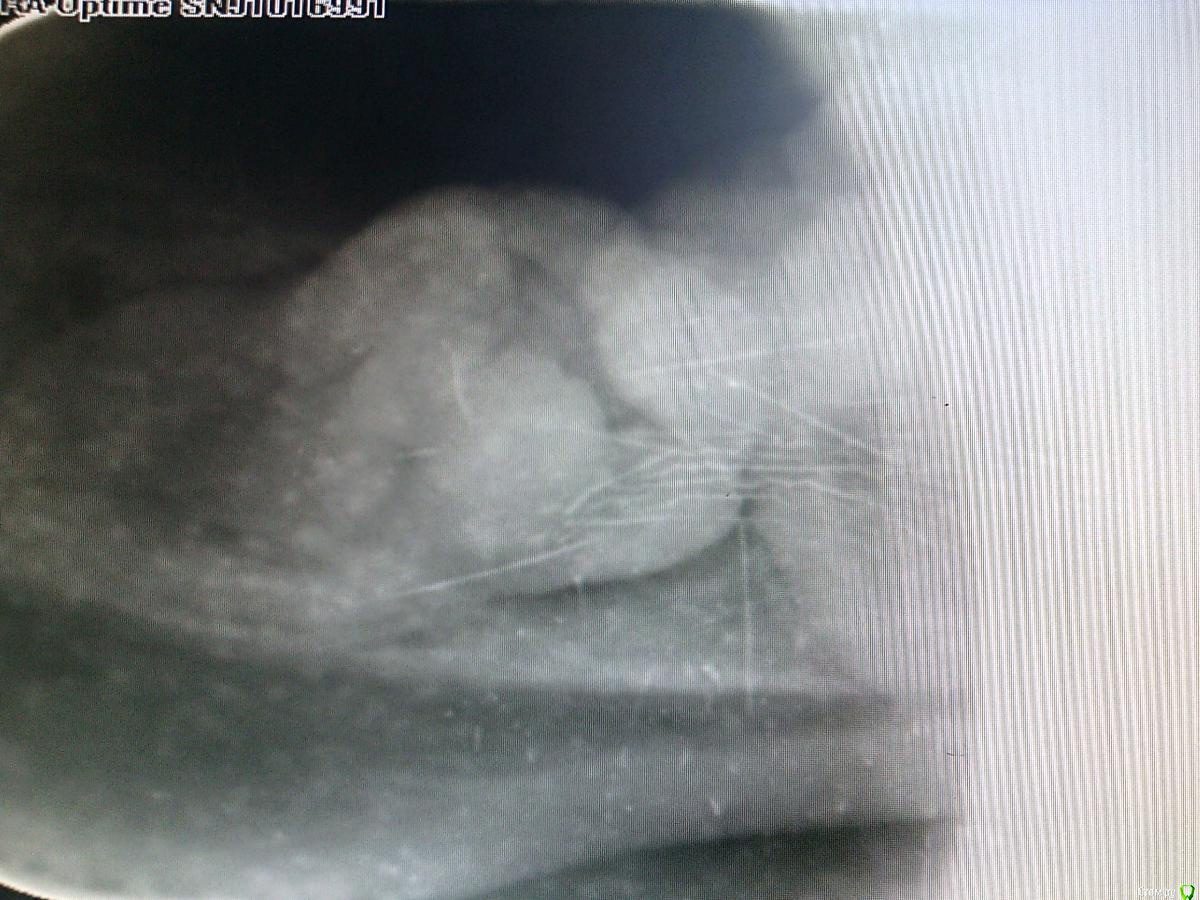

Doc Опубликовано 20 декабря, 2016 Поделиться Опубликовано 20 декабря, 2016 Всем доброго времени суток. Нужно удалить 48, не прорезался, в области медиальных бугров есть микросообщение с полностью рта, туда/оттуда подтекает.Начинаю убирать, все как обычно, оставшиеся корни хотят уйти, но им что то мешает, без резких движений чуть подтягиваю на себя корни и вижу что улов на крючке, точнее на корне, точнее между корней)Корни аккуратно разделил твердосплавом, все убрал, зашил. Парестезии нет, заживает без особенностей. Интересный был случий, разбавил рутину)Круто. Представляю что было бы с этим пациентом, если бы он пришел с этим зубом в какую-нибудь бесплатную поликлинику к доктору, у которого 30 номерков за час пройти должны. Ведь дернули бы и не заметили, что сделали человека инвалидом. 1 Ссылка на комментарий

PaulG Опубликовано 20 декабря, 2016 Поделиться Опубликовано 20 декабря, 2016 Всем доброго времени суток. Нужно удалить 48, не прорезался, в области медиальных бугров есть микросообщение с полностью рта, туда/оттуда подтекает.Начинаю убирать, все как обычно, оставшиеся корни хотят уйти, но им что то мешает, без резких движений чуть подтягиваю на себя корни и вижу что улов на крючке, точнее на корне, точнее между корней)Корни аккуратно разделил твердосплавом, все убрал, зашил. Парестезии нет, заживает без особенностей. Интересный был случий, разбавил рутину)...турбина, микромотор, повышайка?Просто любопытно, кто что предпочитает. Ссылка на комментарий